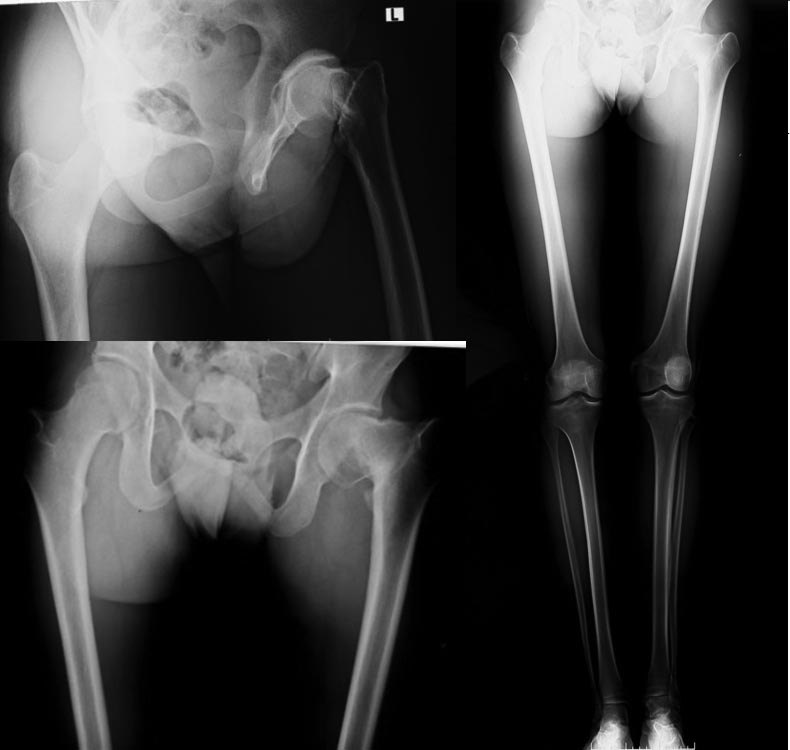

Пациент 18 лет травма в 13 летнем возрасте, остеоэпифезиолиз шейки бедра

лечится консервативно

сейчас. Перелом сросся, беспокоят периодически не очень интенсивные боли при нагрузках. Беспокоит укорочение - 4 см, Что делать - протез? Остеотомия (какая?)? удлинить голень?

Корректно ли поставить диагноз постравматическая koxa vara?

Я думаю, что диагноз "посттравматическая coxa vara". Насчёт того, что сросшийся перелом - надо сделать КТ (что-то не совсем нравятся рентгенограммы, хотя зона перелома и возраст - должно было консолидироваться). Но это был не "остеоэпифизеолиз шейки бедра". На этом уровне нет зоны роста, она гораздо проксимальнее, и с возрастом зона перелома на этом уровне не смещается. Юношеский эпифизеолиз головки бедренной кости и его последствия на рентгенограммах выглядят по-другому. Я не оперирующий врач, но по-моему, здесь нужно эндопротезирование.

Да, вряд ли это эпифизеолиз, там головка бы одна сползла, а тут на уровне основания шейки был перелом.

только не koxa, а coxa, во-1-х. Во-2-х, надо сделать снимок в сгибании в тазобедренном суставе 90 градусов. А лучше бы еще и КТ. И коажется, что это не только варус, а и еще что-нибудь - антекурвация, антеторсия.

Здесь остаточное явление после перелома шейки с внутренней ротацией. Перед операцией надо определиться со степенью ротации шейки трехдименционной КТ и потом планировать операцию.

Правильно заметили, что "не только варус, а и еще что-нибудь - антекурвация, антеторсия". Для исправления укорочения показана вальгусная остеотомия, но здесь, кроме варуса, имеется изгиб в шейке. При наличии только варусной деформации, как предлагает Александр, можно применить гвоздь, но исправление только в одной плоскости может привести к следующей проблеме...

Многоступенчатую коррекцию закрыто трудно выполнить на гвозде! Здесь нужно исправить деформацию и укорочение. Вальгусная остеотомия восстановит укорочение, а ротация в шейке останется.

Для решения всех проблем к вальгусной остеотомии необходимо добавить ротацию шейки. Отсечь вертел и сделать“паз” для имплантата. То же самое в шейке. После остеотомии сперва одевается клинок Blade Plate на вертел, потом в шейку в правильном направлении.